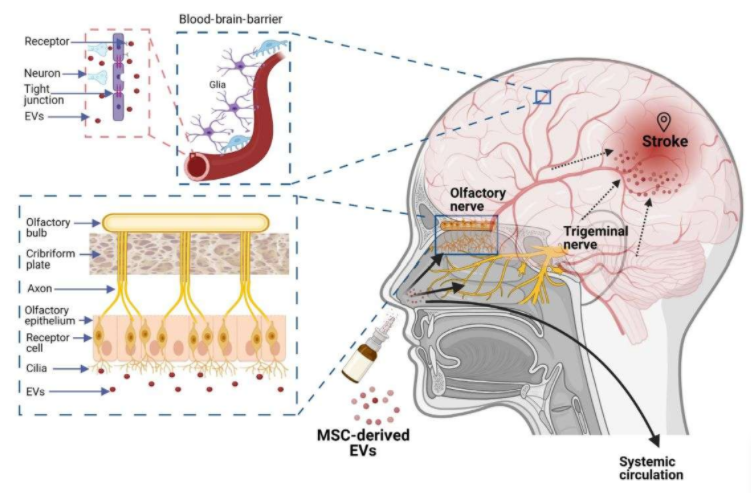

实验显示,经鼻腔递送脂肪来源间充质干细胞(MSCs)的外泌体,能够显著改善神经功能并增强血脑屏障的完整性。

在癫痫方面,美国得克萨斯农工大学的研究团队发现,通过鼻腔滴注的外泌体可在6小时内富集于癫痫病灶区域,并在海马区持续释放活性成分超过72小时。单次给药便能降低58%的炎症因子水平,有效保护关键神经元,长期维持神经的正常发生,并逆转记忆功能障碍。 外泌体经鼻入脑的路径依赖于鼻腔与中枢神经系统之间的特殊解剖连接。借助鼻腔内丰富的血管、淋巴管网以及与脑脊液相通的途径,外泌体可绕过血脑屏障,直接进入脑内病变区域,实现精准的药物递送与修复作用。